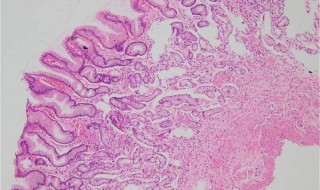

2、胃黏膜肠上皮化生是由慢性胃炎到胃癌发生过程中的重要环节,目前临床诊断主要依赖于内镜检查及胃粘膜活检病理证实。肠上皮化生可与许多胃黏膜病变伴随,如浅表性胃炎、萎缩性胃炎、糜烂性胃炎、胃溃疡可伴有肠上皮化生。

3、慢性萎缩性胃炎通常也会伴有肠化生的现象。胃癌确实可能由肠上皮化生发展而来,但肠上皮化生离胃癌还有很长一段距离。不要因为检查出肠化生就背上思想包袱,焦急忧虑,增加不必要的负担。

胃黏膜上皮细胞癌变并非一朝一夕的事情,并非由正常细胞一跃成为癌细胞,而是一个慢性渐进的过程,

4、在发展成恶性肿瘤之前,常常经历:正常胃黏膜→慢性浅表性胃炎→慢性萎缩性胃炎→不完全小肠型肠化→不完全大肠型肠化→异型增生→早期胃癌→进展期胃癌。如此多年持续的癌前变化。若能及早识别和及早干预,也是一种防止胃癌的有效途径。